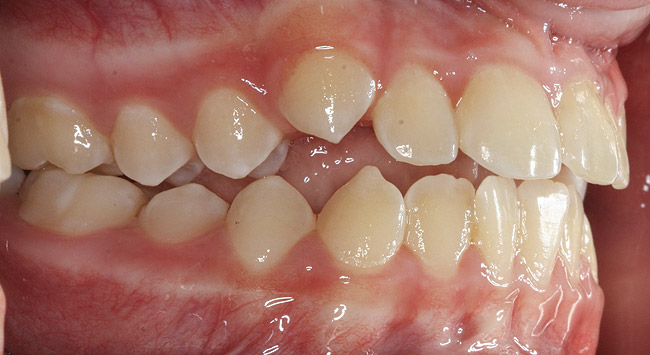

(10.) Narrow maxilla with tooth wear and bilateral crossbite.

Figure 10

(12.) Class II Angle classification with worn dentition and anterior open bite.

Figure 12